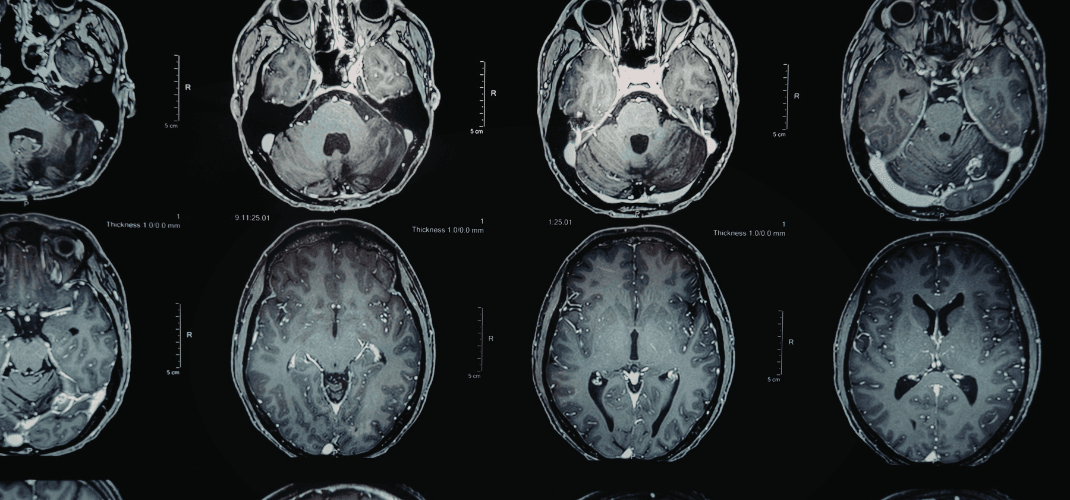

In mild traumatic brain injury litigation, one of the most persistent challenges is the gap between what a patient experiences and what standard imaging shows. When a routine MRI or CT scan returns "within normal limits," it is not the end of the neurological inquiry. For a qualified neuroimaging expert, it is frequently the beginning of a more nuanced evaluation.

Conventional MRI and CT were not designed to evaluate the integrity of white matter microstructure—the vast network of axonal pathways that connects regions of the brain and underlies cognitive function.

Diffusion Tensor Imaging (DTI) operates differently. Rather than producing a conventional anatomical image, DTI measures the movement of water molecules through the white matter tracts.